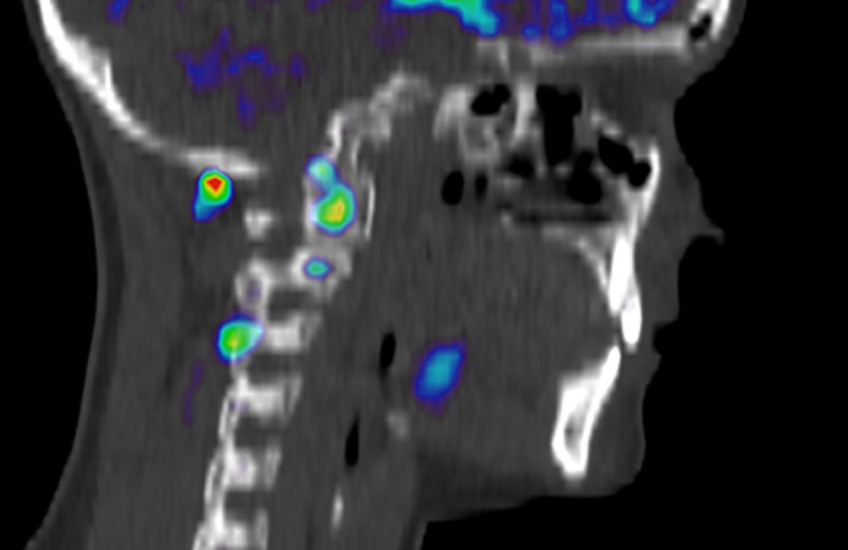

For this study, 16 young adult patients with whiplash injury grade II were recruited at the emergency department and underwent PET/CT scans at the time of their initial hospital visit and at a follow-up six months after injury. For the PET/CT scans, the researchers used a special tracer, [11C]D-deprenyl, that has been shown to help visualize inflammation in other types of musculoskeletal injuries. Eight healthy individuals were also imaged as a control group. Subjective pain levels, self-rated neck disability, and active cervical range of motion were recorded at the two imaging sessions.

The results showed that the molecular aspects of inflammation and possible tissue injuries in muscles and facet joints after acute whiplash injury could be visualized, objectively quantified, and followed over time with [11C]D-deprenyl PET/CT.

The new approach allowed the researchers to see which peripheral structures were affected in whiplash injury, which strengthens the idea that PET detectable organic lesions in peripheral tissue are relevant for the development of persistent pain and disability in whiplash injury, the researchers said.